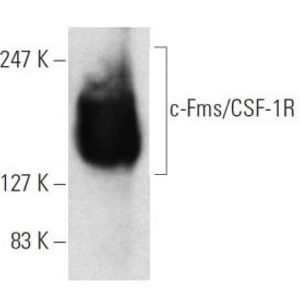

JAN 11, 2021ImmunologyMacrophages are a type of immune cell that can detect and destruct bacteria, viruses, and harmful materials. They a ...